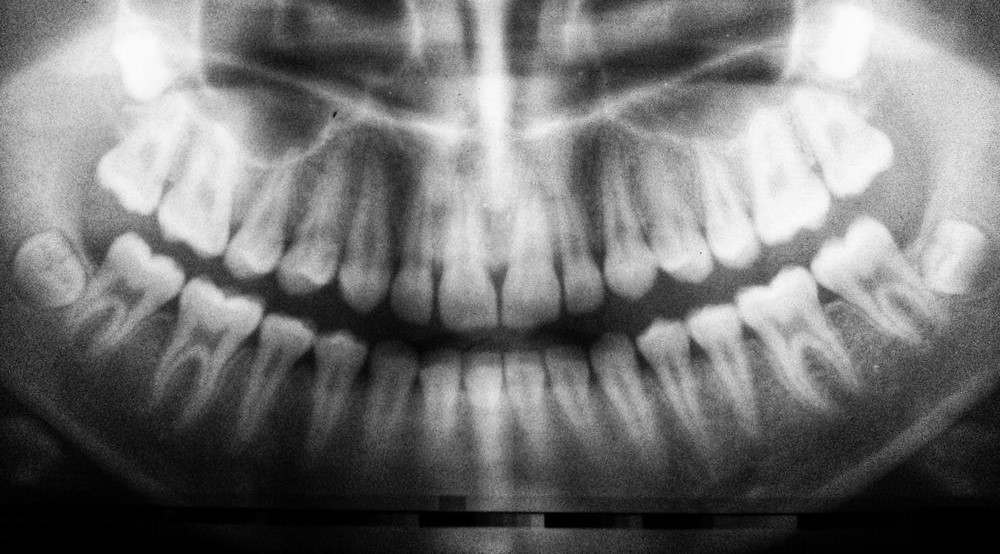

Esses quatro dentes extras, que formam o terceiro conjunto de molares, lá no final da mandíbula, contêm um centro de tecido mole chamado polpa dentária, que mantém o dente vivo.

Quase todos os humanos nascem com dentes do siso, porém, eles são frequentemente extraídos a partir da adolescência, quando pouco dano ao DNA ocorreu dentro da polpa dentária, tornando-os excepcionalmente maleáveis e mais seguros.

O Earth.com afirma que 10 milhões de dentes do siso são removidos todos os anos, e é possível enviá-los para um biobanco na Europa.